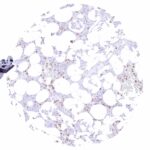

| Respiratory system | Respiratory epithelium | Negative. |

| Lung | Negative. | |